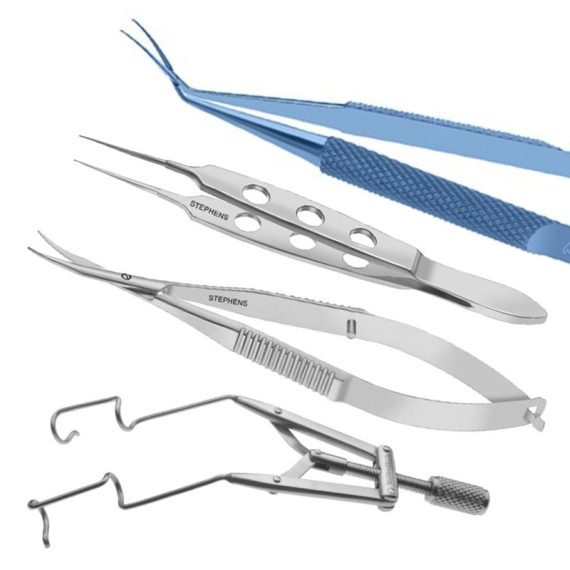

Stephens Instruments instrument rangeStephens Instruments delivers precision-crafted ophthalmic instruments for cataract, corneal,...Code: Explore

Stephens Instruments instrument rangeStephens Instruments delivers precision-crafted ophthalmic instruments for cataract, corneal,...Code: Explore -